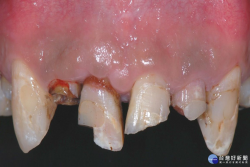

牙齒撞傷需冷靜 找回斷牙保持潮濕盡快就醫

奇美醫學中心牙醫部牙髓病科主治醫師賴曉錞提醒,牙齒撞傷後最重要是維持冷靜,找回斷牙,保持潮濕並盡快就醫。 「男童與同學打籃球碰撞,門牙缺角」、「騎腳踏車遭車撞,跌倒牙齒斷3根」,意外造成牙齒被撞斷的事件時有所聞,有時甚至牽扯到賠償問題,到底牙齒被撞傷後如何治療?只能做假牙,甚至拔掉斷牙而後植牙嗎?奇美醫學中心牙醫部牙髓病科主治醫師賴曉錞說,保持冷靜、...... [閱讀更多]